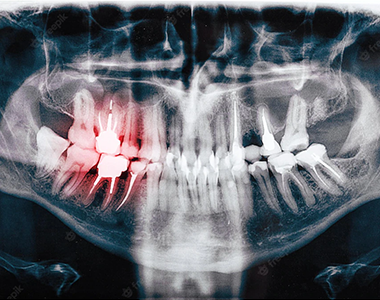

Early tooth decay does not tend to show many physical signs. Sometimes the tooth looks healthy, but your dental team will be able to see from an x-ray whether you have any decay under the enamel, any possible infections in the root, or any bone loss around the tooth.

X-rays can help the dental team to see in between your teeth or under the edge of your fillings. Finding and treating dental problems at an early stage can save both time and money.

In children, x-rays can be used to show where the adult teeth are and when they will appear. They are also used in the same way for adults when the wisdom teeth start to come through.

X-rays can show decay that may not be seen directly in the mouth: for example, under a filling, or between the teeth. They can show whether you have an infection in the root of your tooth and how severe the infection is.

In children, an x-ray can show any teeth that haven’t come through yet, and show the dental team whether there is enough space for the teeth to come through. In adults, it can show any impacted wisdom teeth that may need to be removed, before they cause any problems.